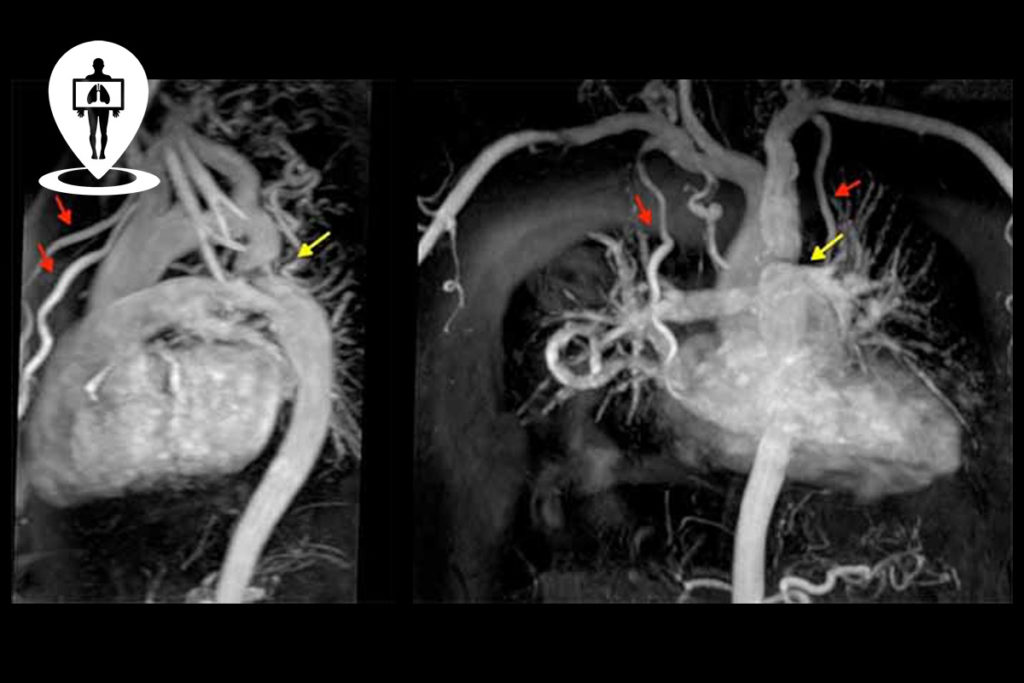

La risonanza magnetica dell’addome superiore è un esame che, fornendo immagini dettagliate e ad alta risoluzione di organi e apparati quali per esempio fegato, milza, pancreas, reni, surreni, permette di documentare condizioni patologiche di diversa origine.. Le cisti sono solitamente abbastanza visibili all’ecografia o alla TC con contrasto, ma l’esame che può dare più informazioni è la risonanza magnetica del pancreas con colangio-risonanza, poiché è in grado di distinguere il contenuto liquido della cisti e la sua eventuale comunicazione con i dotti pancreatici.

PREPARAZIONE. Il paziente deve presentarsi il giorno dell’esame a digiuno da almeno 6 ore e con il risultato recente del dosaggio della CREATININEMIA e possibilmente con il calcolo del filtrato glomerulare (massimo 2 mesi precedenti la data di esecuzione dell’esame o con il modulo di rilevazione anamnestica e consenso al mezzo di contrasto.. La risonanza magnetica con contrasto è un esame diagnostico preciso e affidabile, che permette di studiare nel dettaglio parenchimi, tessuti, vasi sanguigni. È proprio l’uso del mezzo di contrasto che rende questa metodica ancora più specifica e sensibile rispetto alla risonanza magnetica basale, senza impiego del mezzo di contrasto.